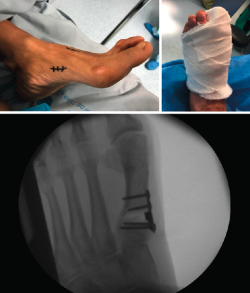

Figura 3. Detalles quirúrgicos de la osteotomía de cierre lateral.

No se objetivó ningún caso de metatarsalgia de transferencia ni de pseudoartrosis. En las Figuras 2 y 3 se pueden ver detalles quirúrgicos de las osteotomías de apertura y cierre.

Figura 5. Caso clínico de osteotomía de cierre (radiología preoperatoria y control a los 4 años).

En las Figuras 4 y 5 se muestra un ejemplo intervenido de osteotomía de apertura y cierre.